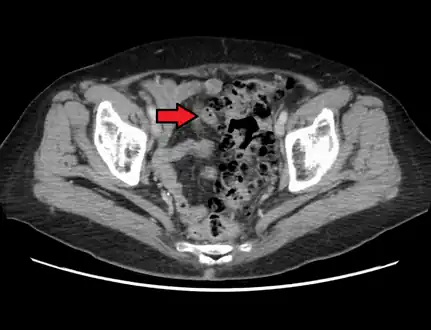

- Contrast CT is the investigation of choice in acute episodes of diverticulitis and where complications exist.

CT scan showing extensive diverticulosis of the sigmoid colon -

Diverticular disease -